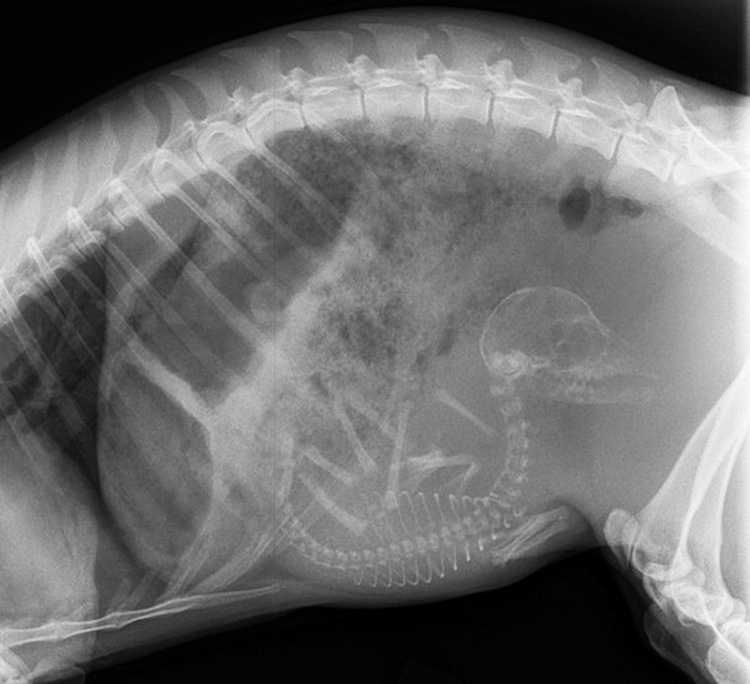

5 – Chienne enceinte. Comme les femmes, les chiennes sont enceintes pendant trois trimestres-chaque 21 jours de long. Autour de 45 jours, il est possible de déterminer au rayon-x combien de chiots feront partie de la portée.